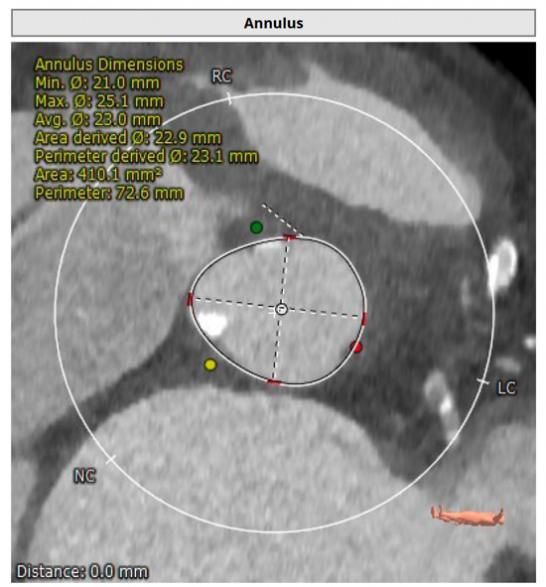

患者为女性,85岁,2013年行冠脉支架植入术,2018年再次行冠脉支架植入术合并房颤冷冻球囊消融术,2020年行永久起搏器植入术。1年前无明显诱因出现间断活动后气促,活动耐力下降,近3月上述症状加重。术前CT显示主动脉瓣为三叶瓣,重度钙化,术前经胸超声主动脉瓣口峰值流速5.7m/s,峰值压差124mmHg,平均跨瓣压差78mmHg,诊断为主动脉瓣重度狭窄伴关闭不全。

术前CT分析结果